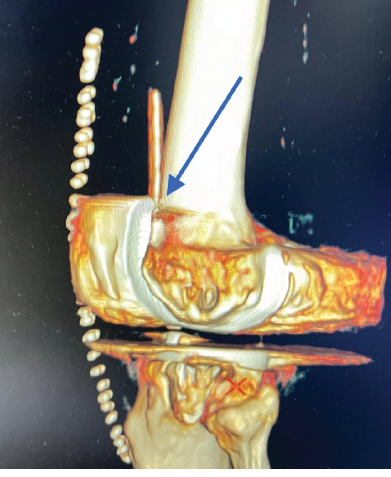

A Displaced and Entrapped Anterior Malleolus (Tillaux Fragment) Causing an Irreducible Syndesmosis and Ankle Fracture–Dislocation in an Adolescent: A Case Report

Ameya H Velankar , Sampat Dumbre Patil , Vaishali Dumbre Patil